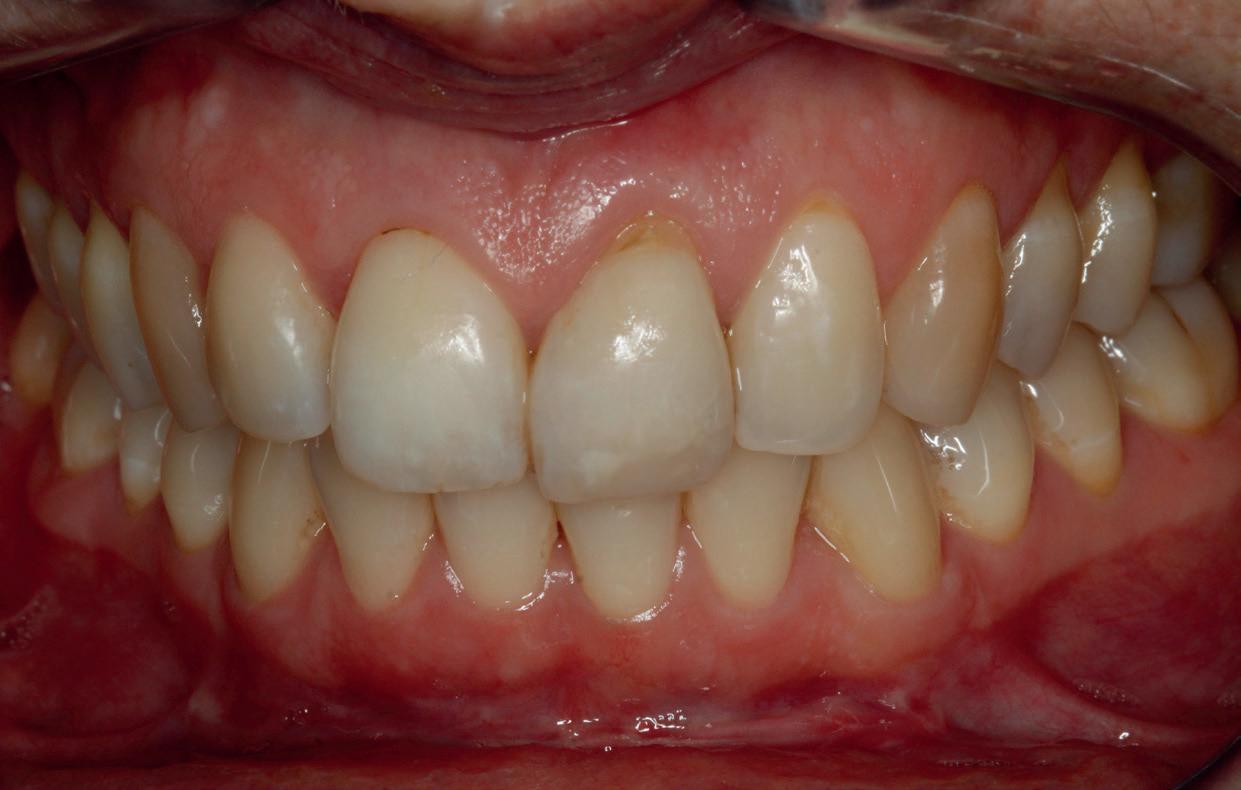

Mevrouw werd naar het Dental Design Center verwezen om een complex probleem aan het bovenfront te beoordelen en indien mogelijk te behandelen. Tien jaar geleden zijn er om esthetische redenen op de 12, 11, 21 en 22 kronen geplaatst. Helaas bleek achteraf een wortelkanaalbehandeling van de 22 noodzakelijk. Na een aantal jaar ontstond er weer een infectie apicaal aan de 22 en werd er een apex uitgevoerd. Helaas had deze behandeling niet het beoogde resultaat. Twee weken voordat ze bij mij op consult kwam, is het element geëxtraheerd en is er een partiële plaat geplaatst als tijdelijke oplossing (foto 1-3).

Na de IPP (esthetisch/functionele) analyse blijkt dat de gezichts- en faciale mediaan niet geheel overeenkomen en dat de gingiva lijnen van het bovenfront niet helemaal parallel lopen met de interpupillaire lijn. Na overleg met mevrouw kiest zij ervoor om dit niet orthodontisch te laten corrigeren. Mevrouw

heeft de nadrukkelijke wens om geen brugconstructie te krijgen. Om die reden is een etsbrug of een conventionele brug geen optie. Daarom bestaat het behandelvoorstel uit vier losse kronen waarvan de 22 implantaat gedragen zal zijn. Een gedetailleerd onderzoek van de regio 22 is noodzakelijk (foto 4-6).

Bij de evaluatie van deze casus blijkt dat het herstellen van de processen alveolaris ter plaatse van de 22 is gerealiseerd en dat de gingiva qua positie en volume rond de 22 en 23 is verbeterd. Het implantaat is goed ge-osseointegreerd en de gingiva rond het implantaat heeft een natuurlijke vormgeving gekregen. De kronen zijn met moderne technologie en esthetisch hoogwaardig vervaardigd door het Oral Design Center Holland. Met dank aan Eric van der Winden.

De dentale mediaanlijn is rechtop gezet, maar staat niet helemaal gelijk met de faciale mediaan. Echter, mevrouw is functioneel en esthetisch naar tevredenheid afbehandeld (foto 27-30).